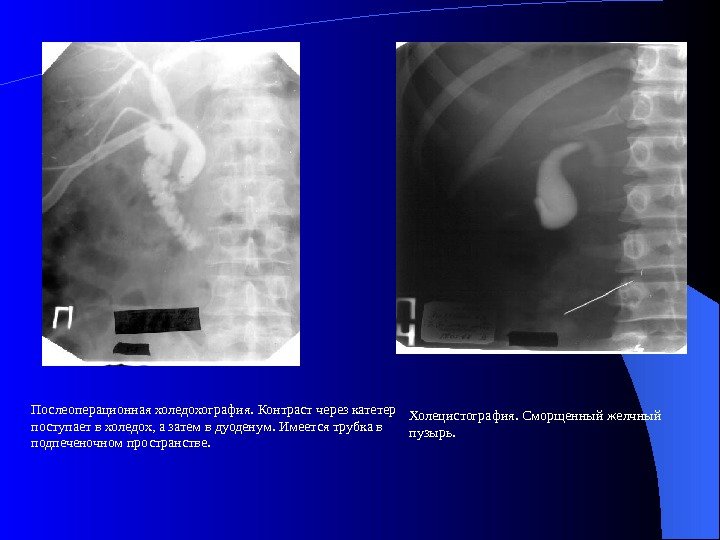

Каким образом определить наличие у себя такого неприятного заболевания? Главное – своевременно обратиться за врачебной помощью. Специалист назначит Вам контрастное аппаратное обследование, которое поможет установить точный диагноз. Рентгенолог даст выпить контрастное жидкое вещество, а затем с помощью рентгеновской аппаратуры он сможет узнать, есть в этом органе желчь или она туда не поступает. Если этого печеночного серкета в пузыре нет – он просто не функционирует (отключился).

Для уточнения диагноза, как правило, используется методика УЗИ-диагностики, с помощью которой специалист определяет форму и размер пораженного органа. Кроме того, такое исследование позволяет определить текущее состояние этого желчного резервуара. Он может или не работать совсем, или работать с перебоями, может быть сморщенным или находится в нормальной форме. При отключении желчного пузыря в нем никогда нет внутри желчи, и он никогда не способен самостоятельно сокращаться. Кроме такого, такое исследование помогает обнаружить в этом органе опухоли и камни.

Совсем неработающий желчный пузырь на снимке будет не виден. В подпеченочной области будет заметно лишь небольшое темное пятно.

Если же в этом внутреннем органе еще есть жёлчь, то этот его участок будет выглядит более светлым, а над этим пятнышком будет видна плотная стенка. Спавшийся желчный пузырь рассмотреть на снимке практически невозможно. Если орган имеет сморщенность, то контуры такого желчного пузыря будут неправильными и неровными.